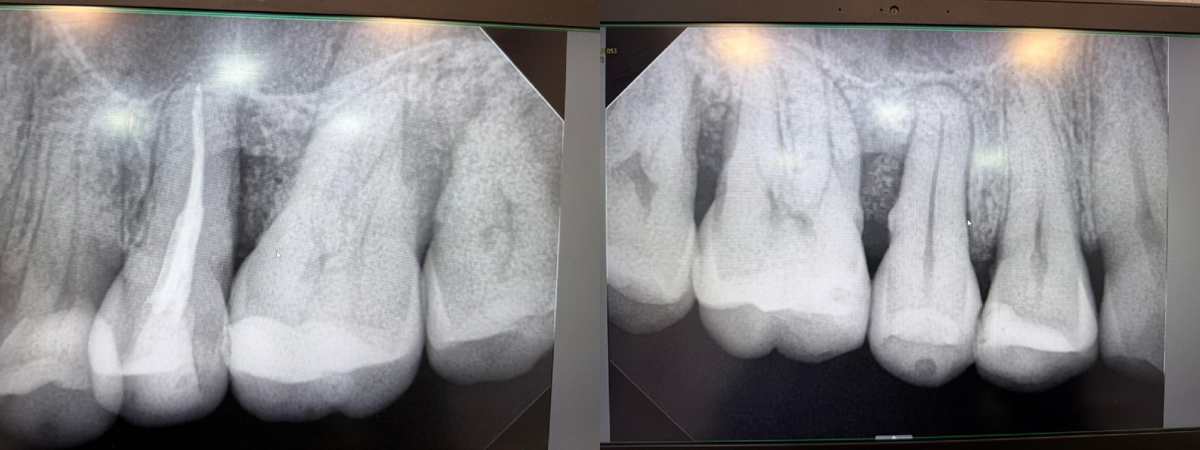

Пациент пришёл с диагнозом пародонтита и выраженными костными дефектами.

На первом снимке видно: опорные ткани разрушены, корни стоят в "провалах", прогноз кажется слабым даже неискушённому глазу.

наглядное до/после нашего пациента